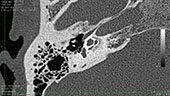

La diagnosi è agevole in presenza di una ipoacusia trasmissiva o mista e una membrana timpanica di aspetto normale. Le indagini radiologiche TC, effettuate con apparecchiature ad alta risoluzione, possono evidenziare la presenza dei focolai otosclerotici.